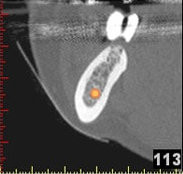

(siehe Bild 3 und 4).

Mit diesen gewonnenen Informationen und Planungen stellt der Zahnarzt interaktiv spezielle Bohrschablonen her. Diese ermöglichen eine exakte Positionierung der Implantate, so wie vorher am Computer geplant.

Weiterhin ist eine auf diese Weise geplante Operation für den Patienten weit weniger belastend. Denn die Freilegung des Knochens ist auf ein Minimum reduziert.